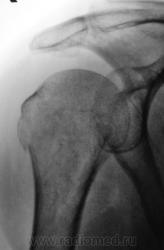

Травма.   Пациентка направлена на рентгенографию плечевого сустава.

Давно любимый вколоченный перелом х/шейки.